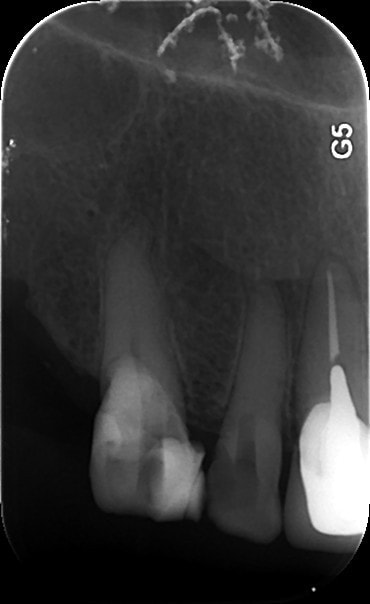

1   02022015 xhyug0 - Eugenol

3   02022015 athoja - Eugenol

2   02022015 jomvv1 - Eugenol

4   06022015 zewfwa - Eugenol

5   06022015 uym87j - Eugenol